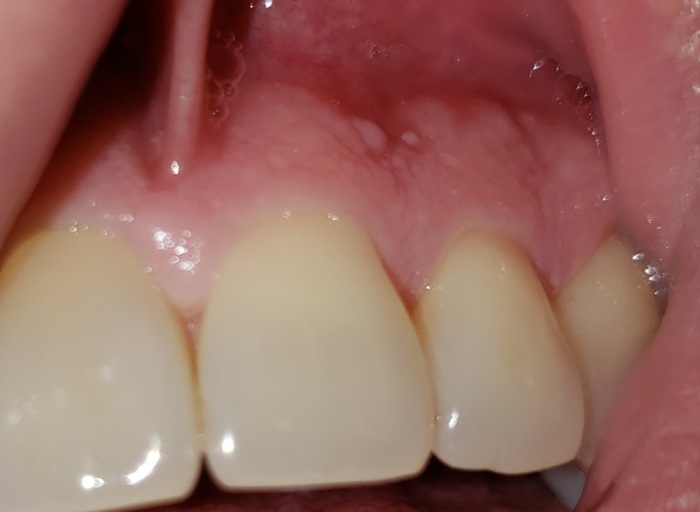

Infection and Bump on Gums

My daughter must of had a infection she did not inform me about. She just called me and said the bump on her gums popped and yellow stuff came out and it feels fine now. Should I rush her to the hospital or could it wait about 4 days into I take her to the dentist?

Having such a large infection in the mouth can be extremely dangerous. Even though the abscess has ruptured and drained, this is temporary and the infection (the tooth) is still present in her mouth. The relief she is feeling is temporary, as the pressure that was built up has been relieved temporarily. This infection can very quickly get into the blood stream and run throughout the body. It is important to see your general dentist immediately in order to be properly treated and receive a prescription for antibiotics. The infection will continue to come back and many times, worse than the first. It is not advisable to wait.